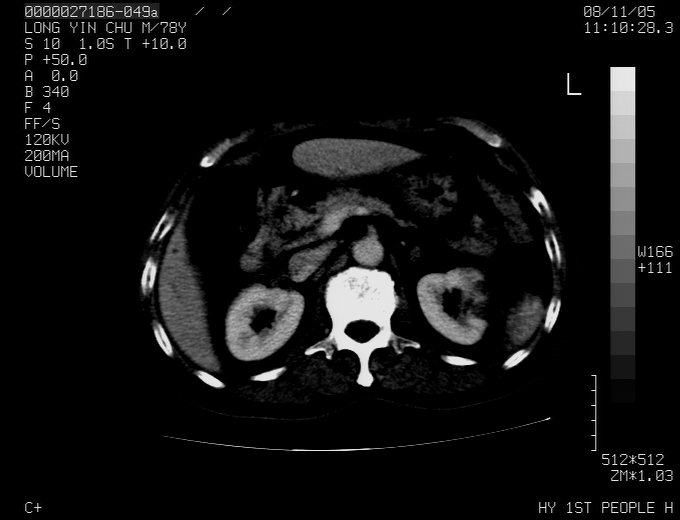

标题: CT16532:M78Y,肝脏病变,请会诊

腹胀,腹痛就诊,男性,78岁,外院b超未见异常。

考虑弥漫性肝癌并脾及双肾转移.双侧胸水.

肝脾肾转移瘤可能性大,左肾不除外梗塞,双侧胸水

考虑肝癌并双肾及脾脏转移;双侧胸腔积液。